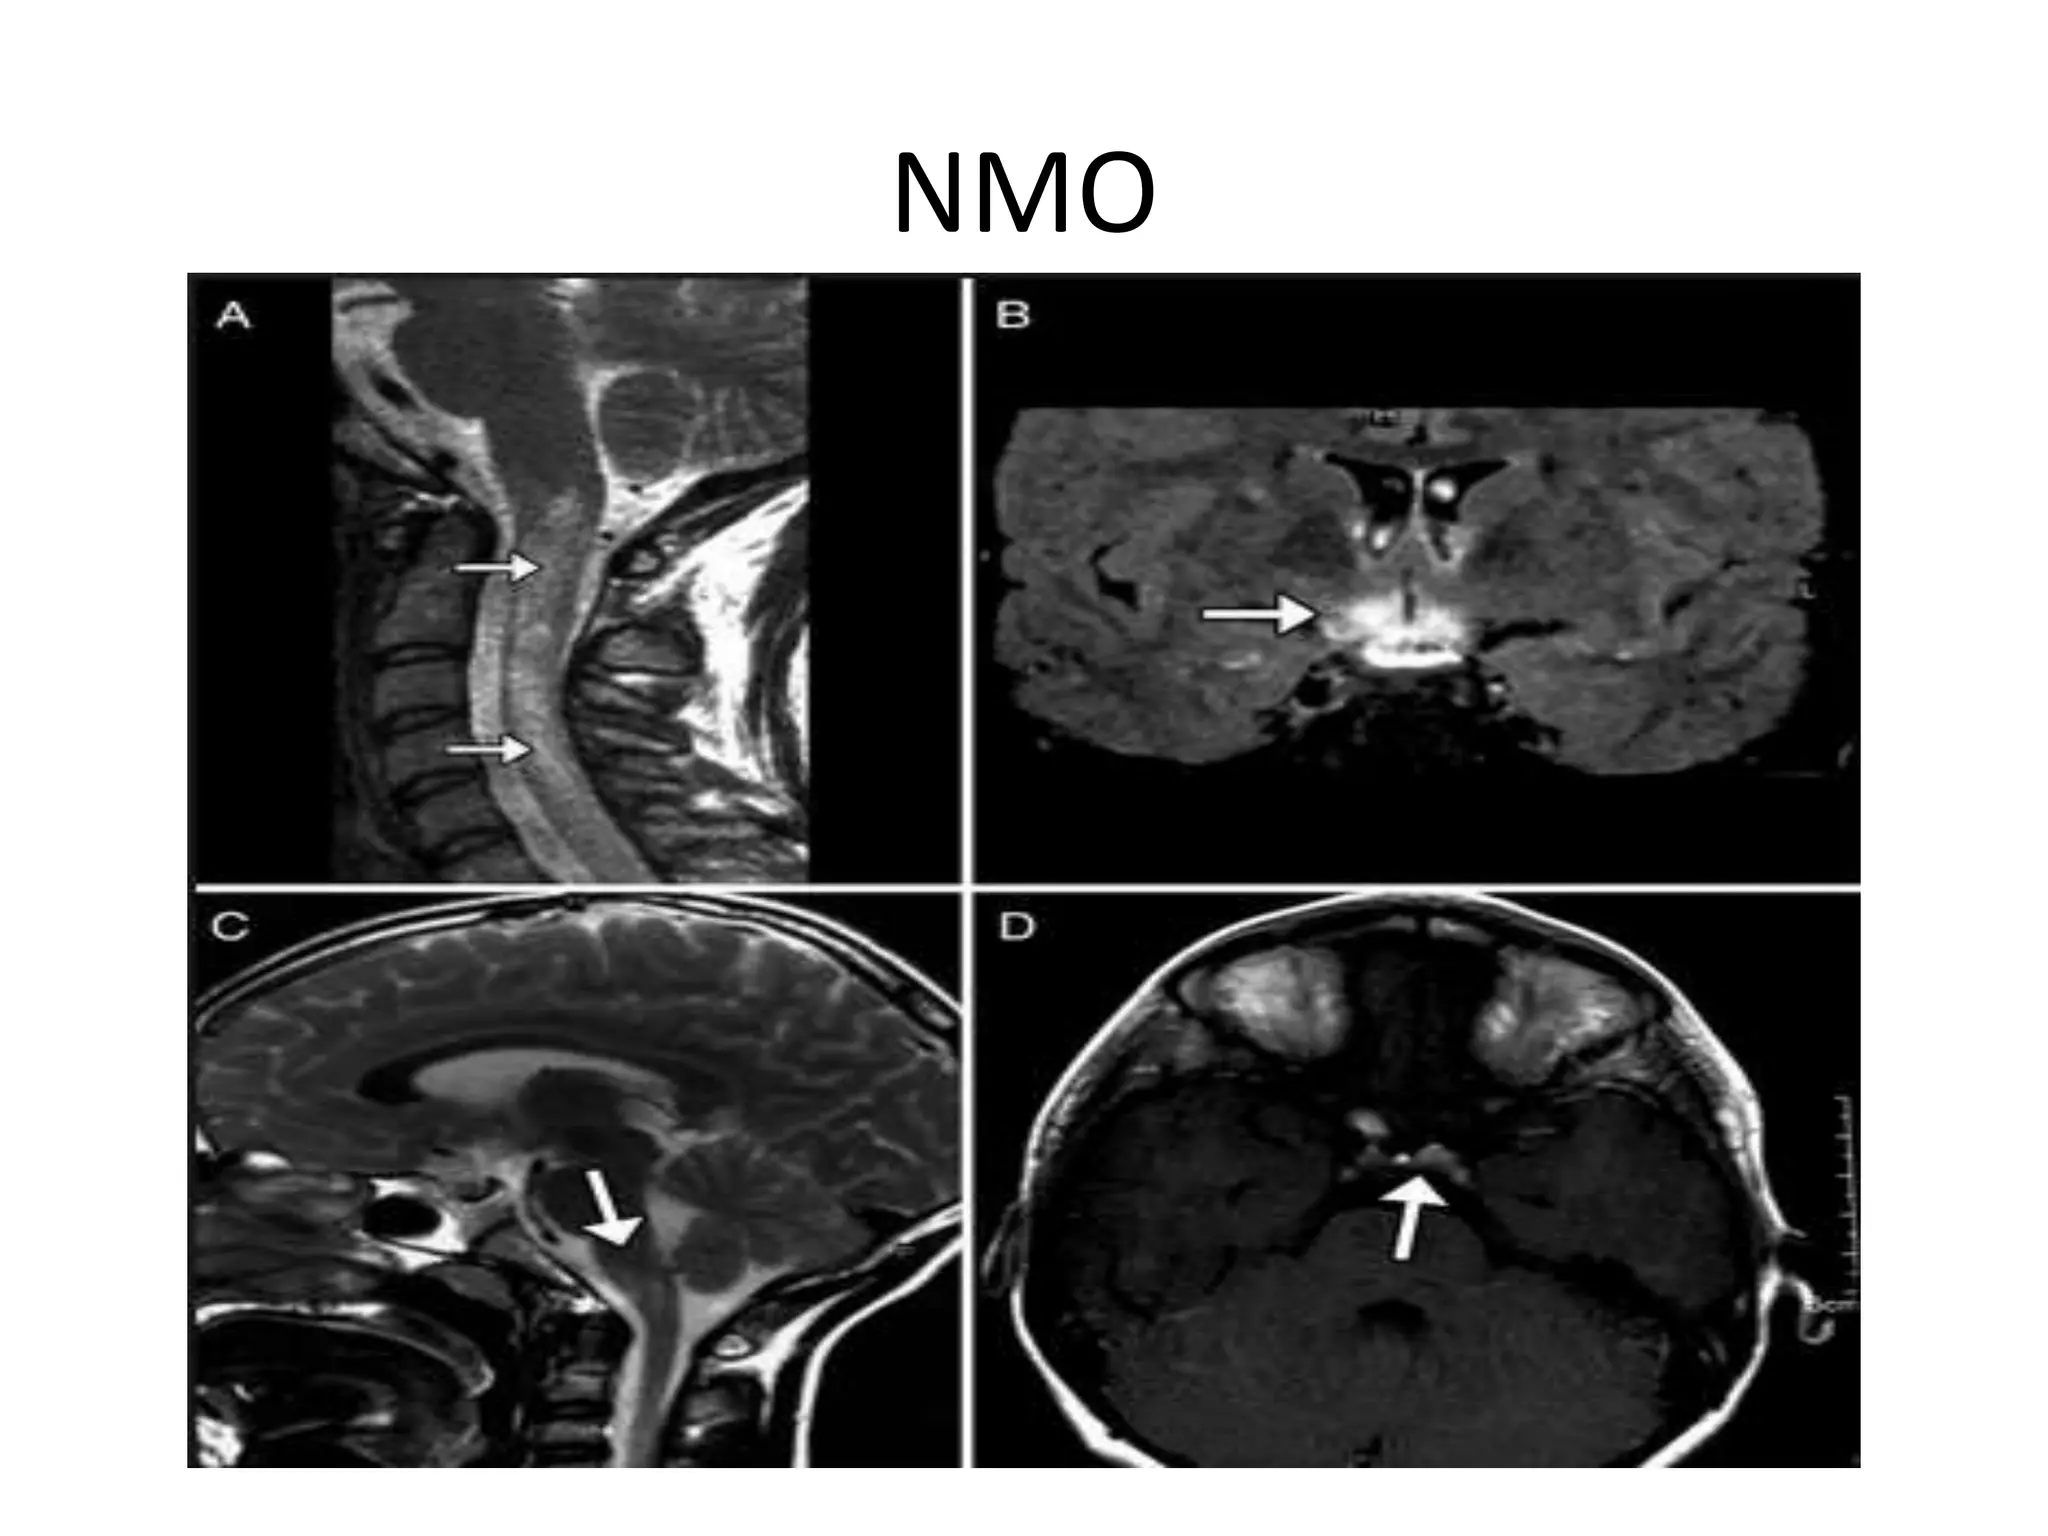

SPINAL CORD

• MC cervical cord is involved

• Hyperintense lesion that extends over three or

more consecutive segments and much of the

cross section of spinal cord

• Lesions may enhance with gadolinium for

several months

• Lesions can progress to atrophy and necrosis,

leading to syrinx like cavities

Abnormal signal in the spinal cord with

swelling and some enhancement.